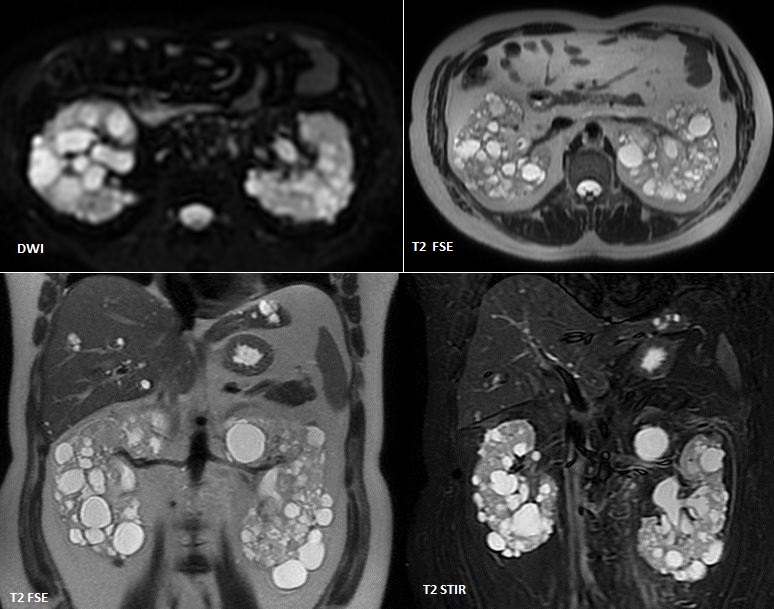

La enfermedad renal poliquística autosómica dominante (ADPKD), la enfermedad renal poliquística autosómica recesiva (ARPKD) y el riñón displásico multicístico presentan características distintivas en la ecografía neonatal.

1. Enfermedad renal poliquística autosómica dominante (ADPKD):

En neonatos, la ADPKD puede mostrar riñones agrandados con múltiples quistes de diferentes tamaños en la corteza y la médula renal. La ecogenicidad cortical puede estar aumentada y la diferenciación corticomedular puede estar disminuida o ausente en casos severos. Aunque la ADPKD es más comúnmente diagnosticada en adultos, puede ser detectada prenatalmente en algunos casos.[1-2]

La ecografía es una herramienta crucial para diferenciar estas condiciones en neonatos, permitiendo una evaluación detallada de la estructura y la ecogenicidad renal, así como la identificación de quistes y su distribución.